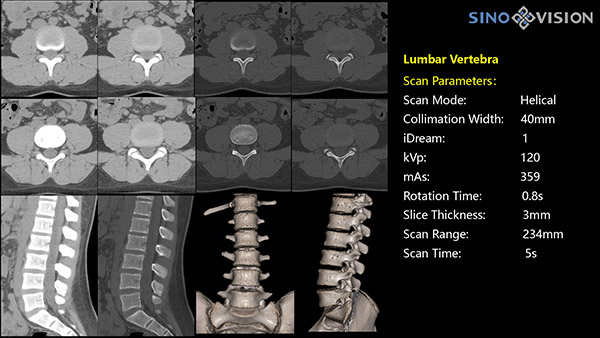

Инновационный 128-срезовый компьютерный томограф SinoVision InsitumCT 568 – это сочетание высокой скорости работы, низкой дозы и максимума возможностей для подавляющего большинства клинических случаев, как в рутинных, так и в углубленных специализированных исследованиях, в том числе педиатрические и кардиологические исследования при сверхнизких дозах.

Полнофункциональный 128-резовый компьютерный томограф InsitumCT 568 - это лучшее в новом поколении широкодиапазонных томографов с 128 срезами и большой диафрагмой. Этот КТ-сканер с большой апертурой обеспечивает 128 срезов КТ с диафрагмой 76 см, улучшает разрешение изображения до 21Lp/cm, помогает точно диагностировать и лечить заболевания, а также значительно улучшает клинические характеристики и расширяемость оборудования. Позволяет реализовать визуализацию в высоком разрешении и в малых дозах лучевой нагрузки.

Полнофункциональная платформа клинической диагностики может точно определять местонахождение и диагностировать общие повреждения качественно и количественно, а также достигать полнофункциональных клинических показателей, включая обширные кардиологические исследования со сверхнизкими дозами лучевой нагрузки.